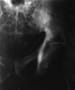

Classic histology of extramammary Paget disease (EMPD). Clusters of large cells with pale, vacuolated cytoplasm scattered throughout the epidermis.